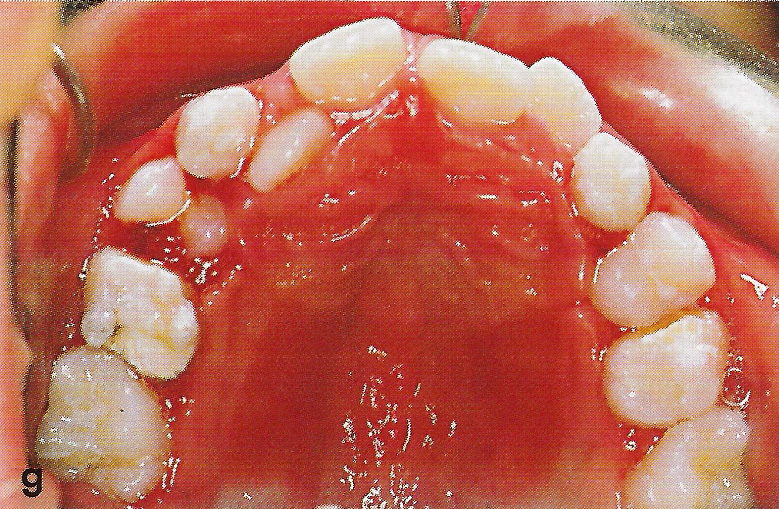

Der Schienungsdraht wurde 4 Wochen nach dem Eingriff entfernt (Abb. 9). 8 Wochen nach der Replantation waren die Milcheckzähne absolut immobil und ergaben einen hellen Kopfschall bei Perkussion, so daß von einer Ankylosierung ausgegangen werden konnte.

• Ankylose Abb.9

Abb. 9 Zustand 4 Wochen nach der Replantation und Entfernung des Stabilisierungsdrahtes. Die Milcheckzähne sind reaktionslos eingeheilt.